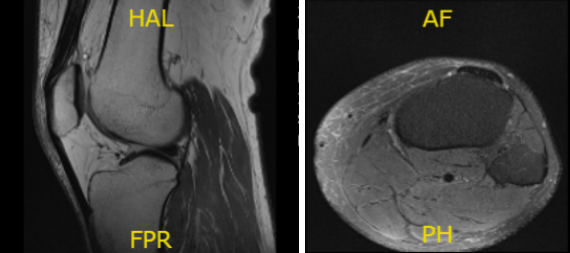

MRI presented and reviewed by the doctor. It showed that the left knee of the patient is intact in medial and lateral meniscus and has no acute osseous injury but has small joint effusion. The central trochlea has a focal chondral fissure and fibrillation in the midportion of the medial femoral condyle.

However, the right knee of the patient, prior partial lateral meniscectomy with diminutive anterior horn with a re-tear in the body of the lateral meniscus. Because of the extrusion of the body the lateral meniscus causes too mild to moderate tricompartmental osteoarthritis with small joint effusion.

The left knee x-ray that completes with patella shows that there are no acute fractures and significant degenerative changes while the right knee has no fractures but have mild osteoarthritic degenerative changes.